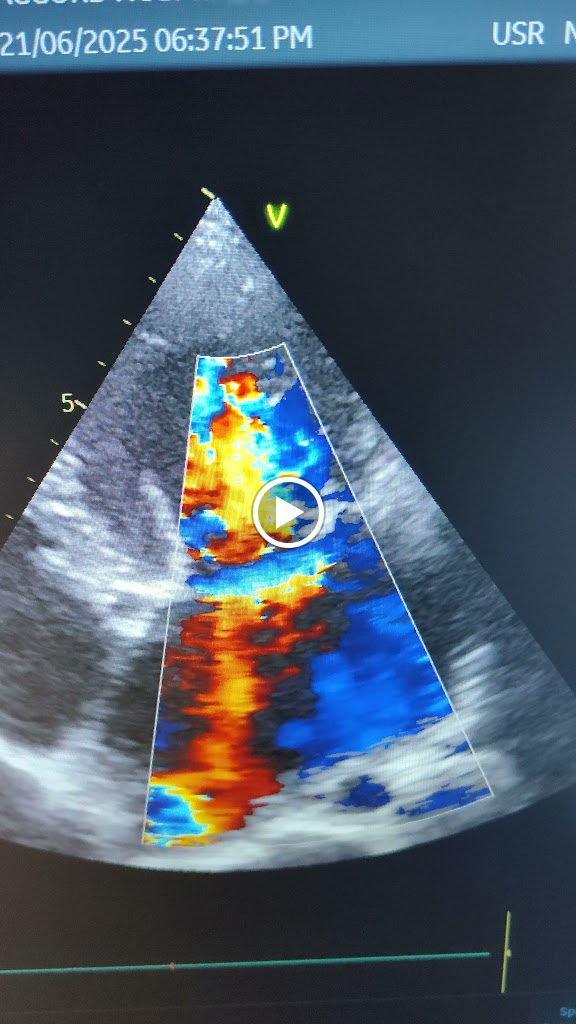

Cardiology, Angiography, Angioplasty Pacemaker, Peripheral Angiography, Peripheral Angioplasty, ASD device closure, VSD device closure, PDA device closure, Ballon Mitral Valvotomy